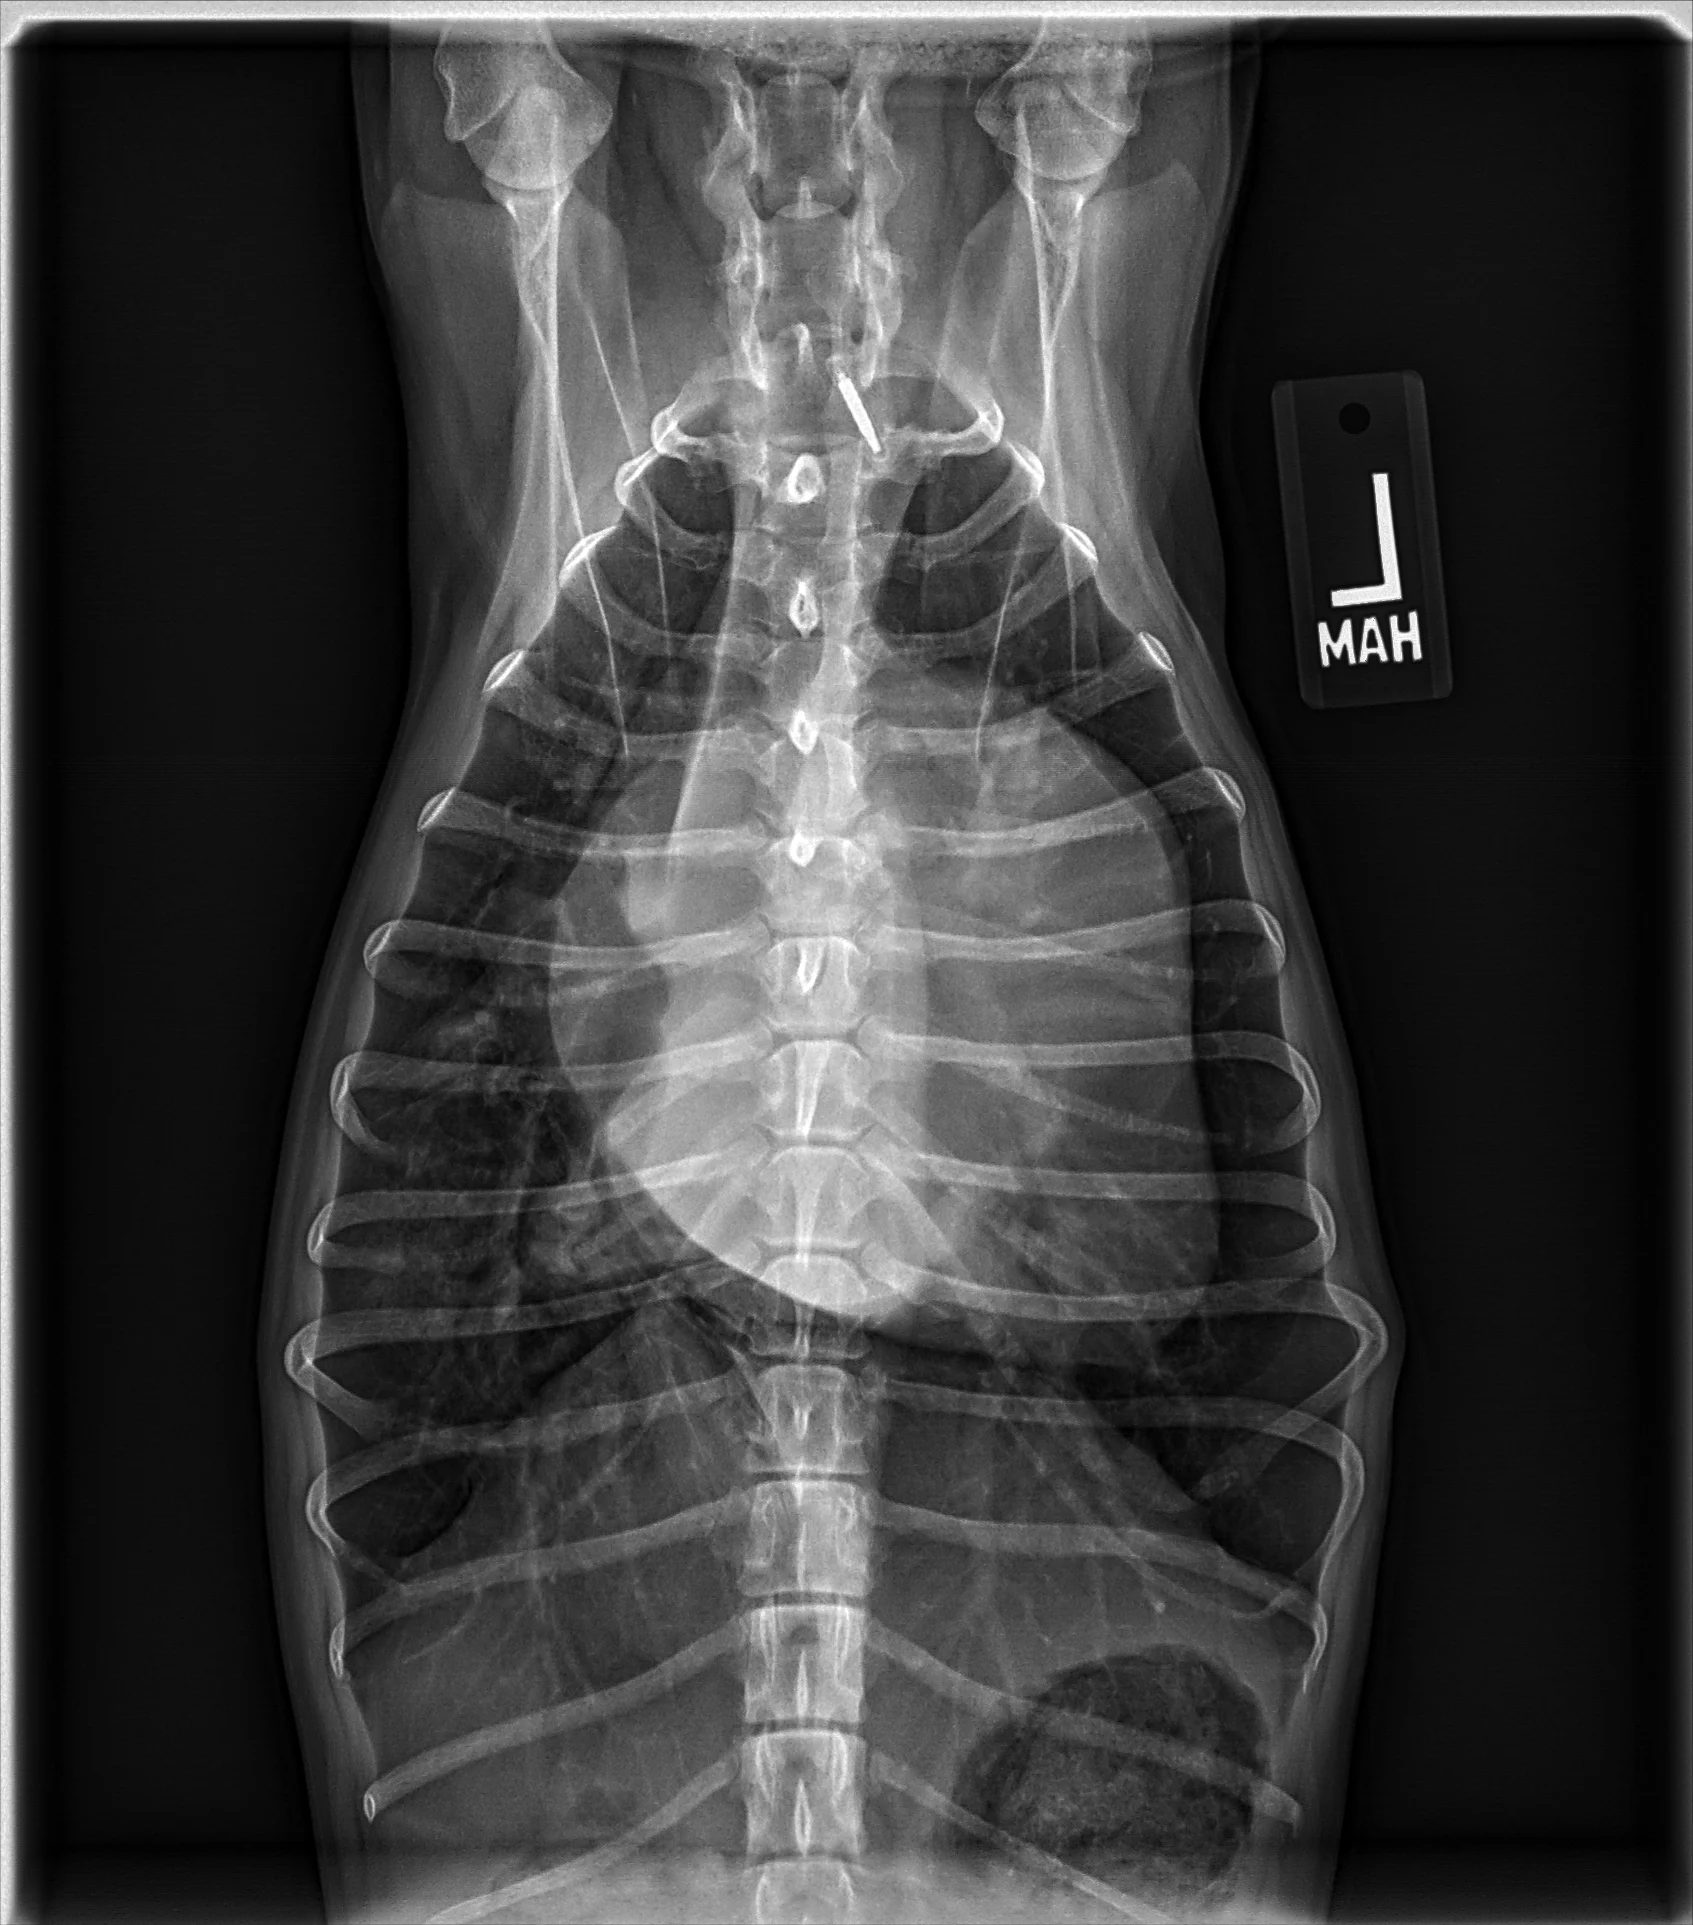

At least 2 orthogonal views, ideally taken during peak inspiration, are necessary for appropriate radiographic study of the cardiovascular system; however, a 3-view study is ideal for comprehensive evaluation of the thorax. Some differences should be considered when deciding to acquire a right versus left lateral projection and a dorsoventral (DV) versus ventrodorsal (VD) projection. On the left lateral view, the cardiac silhouette is typically more rounded and the apex is further elevated from the sternum than in the right lateral view (Figure 1). In the DV view, the cardiac silhouette is commonly displaced cranially and to the left by the diaphragm and appears more rounded than in the VD view. The caudal pulmonary vasculature is better delineated in the DV view, whereas the lung field (particularly the accessory lobe) is better evaluated in the VD view (Figure 2).

FIGURE 1 Normal right and left lateral projections of the thorax in a large, crossbreed dog. The difference in the cardiac silhouette and the apex elevation (arrow) from the sternum in the left lateral view can be seen. VHS, VLAS, modified VLAS (M-VLAS), and VRHi collected from the right lateral view are 10.6, 1.7, 2.8, and 3, respectively, and 10.6, 1.5, 2.9, and 3.4, respectively, collected from the left lateral view. Given these differences, serial radiography should be performed using the same lateral view if only one view is used. In some dogs, roundness of the cardiac silhouette in the left lateral view can be pronounced and misinterpreted as right-sided heart enlargement, particularly if compared with a prior right lateral view. Images courtesy of Federico Villaplana Grosso, DACVR, DECVR